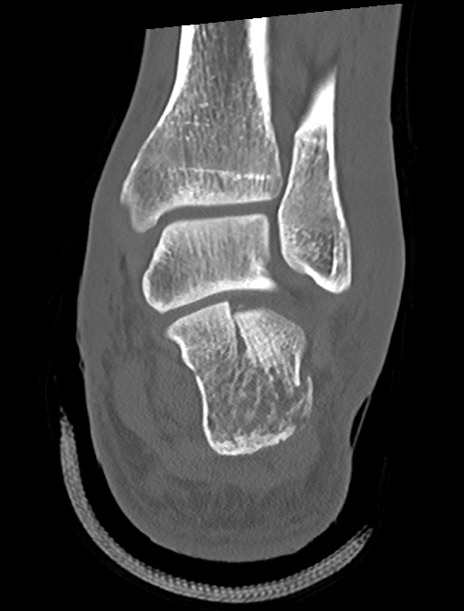

症例37 左足関節CT(冠状断像)

左足関節CT